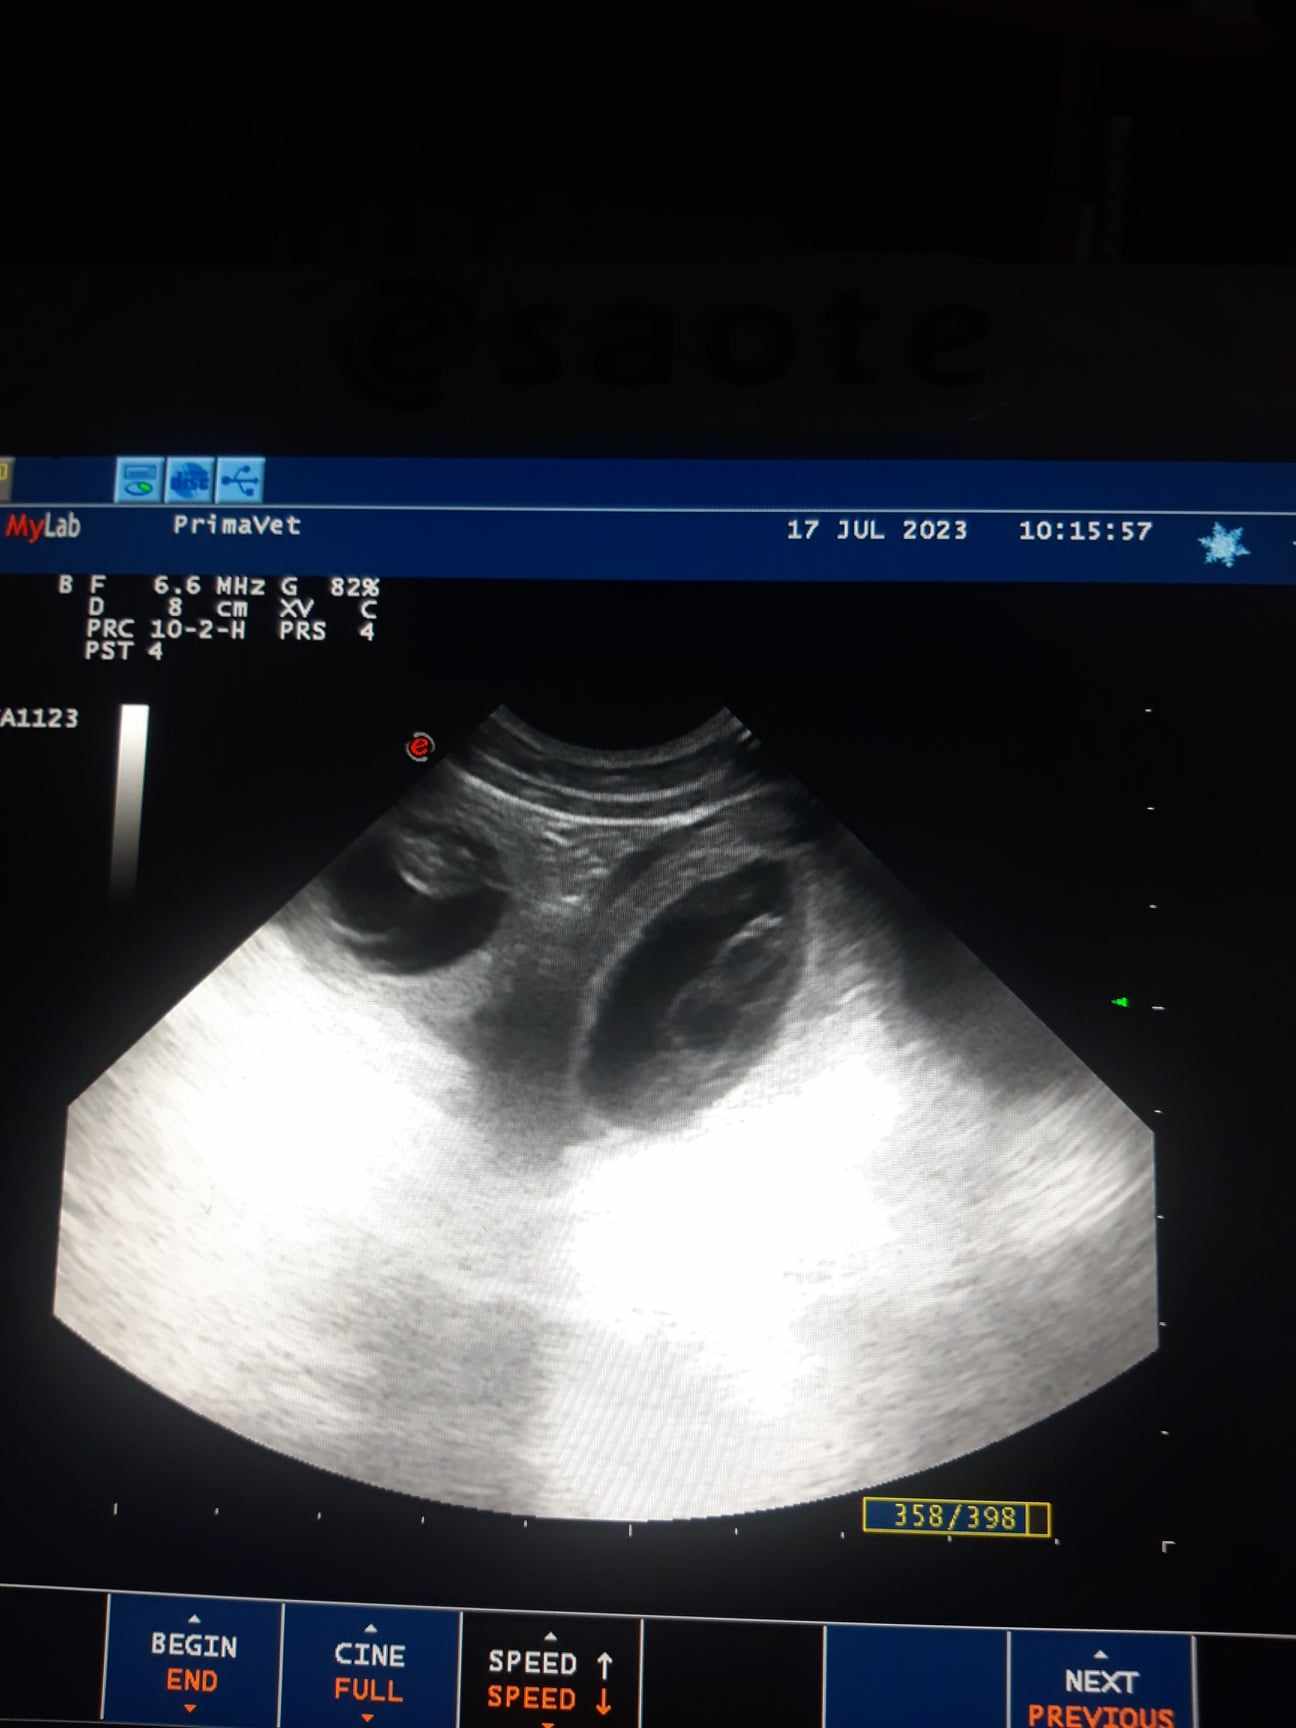

Lorelai a Cai mají potvrzenou březost štěnátka vrhu "U"se narodí cca 6.3.2024